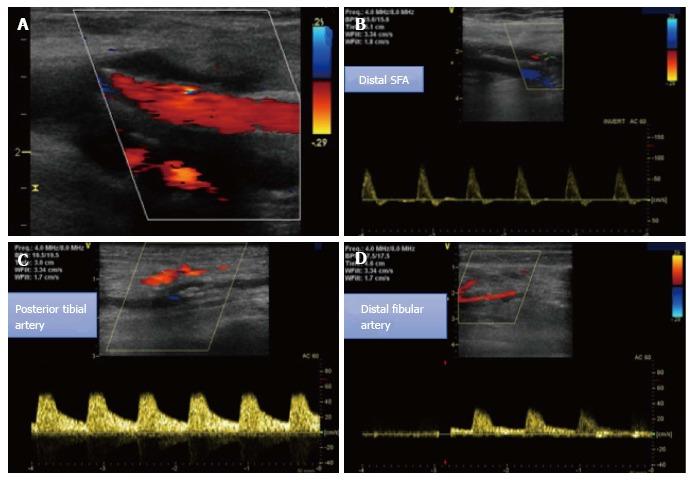

Patients with critical limb ischemia necessitate immediate intervention to restore blood flow to the affected limb. Endovascular procedures are currently preferred for these patients. We describe the case of an 80-year-old female patient who presented to our department with ischemic rest pain and ulceration of the left limb. The patient had history of left femoral popliteal bypass surgery, femoral thromboendarterectomy and patch angioplasty of the same limb 2 years ago. Doppler sonography and magnetic resonance angiography revealed an occlusion of the left superficial femoral artery (SFA) and popliteal artery and of all three infra-popliteal arteries. Due to severe comorbidities, the patient was scheduled for a digital subtraction angiography. An antegrade approach was first attempted, however the occlusion could not be passed. After revision of the angiography acquisition, a stent was identified at the level of the mid SFA, which was subsequently directly punctured, facilitating the retrograde crossing of the occlusion. Thereafter, balloon angioplasty was performed in the SFA, popliteal artery and posterior tibial artery. The result was considered suboptimal, but due to the large amount of contrast agent used, a second angiography was planned in 4 wk. In the second session, drug coated balloons were used to optimize treatment of the SFA, combined with recanalization of the left fibular artery, to optimize outflow. The post-procedural course was uneventful. Ischemic pain resolved completely after the procedure and at 8 wk of follow-up and the foot ulceration completely healed.

严重肢体缺血患者需要立即进行干预以恢复患肢的血流。目前,血管内介入手术是这类患者的首选治疗方法。我们描述了一名80岁女性患者的病例,该患者因左下肢缺血性静息痛和溃疡前来我院就诊。患者2年前曾接受左股腘动脉搭桥手术、股动脉血栓内膜切除术及同肢体的补片血管成形术。多普勒超声和磁共振血管造影显示左股浅动脉(SFA)、腘动脉以及所有三支腘下动脉均闭塞。由于存在严重的合并症,该患者计划接受数字减影血管造影检查。首先尝试顺行入路,但闭塞部位无法通过。在重新评估血管造影图像后,发现在SFA中段水平有一枚支架,随后直接对其进行穿刺,从而实现了闭塞部位的逆行通过。此后,对SFA、腘动脉和胫后动脉进行了球囊血管成形术。结果被认为不太理想,但由于使用了大量造影剂,计划在4周后进行第二次血管造影。在第二次手术中,使用药物涂层球囊对SFA进行优化治疗,并对左腓动脉进行再通以优化流出道。术后过程顺利。术后缺血性疼痛完全缓解,随访8周时足部溃疡完全愈合。